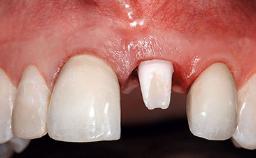

Replacement of an Ankylosed Upper Left Central Incisor: Bone Augmentation and Socket Grafting, Late Placement of an RC Bone Level Implant

A 15-year-old male patient was referred to us by his pediatric dentist in June 2004 for evaluation of treatment options for his failing tooth 21. The patient had recently seen an endodontist for internal bleaching and been advised that there had been significant resorption and ankylosis. The patient’s mother was concerned because the tooth appeared shorter than the adjacent one. His past dental history was significant for trauma (September 2001), where the tooth had been avulsed and reimplanted. Teeth 11 and 21 had been endodontically treated.